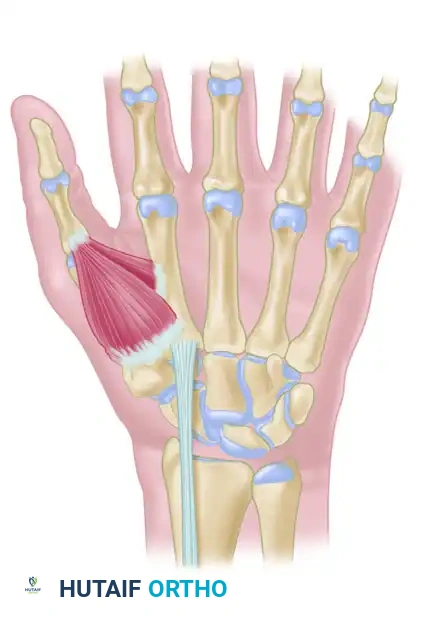

The trapeziometacarpal (TMC) joint of the thumb is a highly specialized biconcave saddle joint that affords the thumb its unique wide range of motion, including flexion, extension, abduction, adduction, and opposition. However, this mobility comes at the cost of inherent osseous instability. The primary static stabilizer of the TMC joint is the anterior oblique ligament (AOL), also known as the volar beak ligament.

Attenuation or traumatic rupture of the AOL leads to dorsal and radial subluxation of the first metacarpal base under the deforming forces of the abductor pollicis longus (APL) and adductor pollicis. Over time, this altered kinematics results in eccentric cartilage wear, volar beak osteophyte formation, and progressive osteoarthritis.

Trapeziometacarpal ligament reconstruction, originally popularized by Eaton and Littler, aims to restore the stabilizing function of the AOL using a distally based strip of the flexor carpi radialis (FCR) tendon. For more advanced disease, modifications such as the Calandruccio ligament reconstruction and tendon interposition (LRTI) or distraction arthroplasty are indicated.

Figure: Schema of ligament support. The key volar ligament is a reflection of the transverse carpal ligament after insertion into the crest of the trapezium. Note the FCR passing directly beneath this ligament.